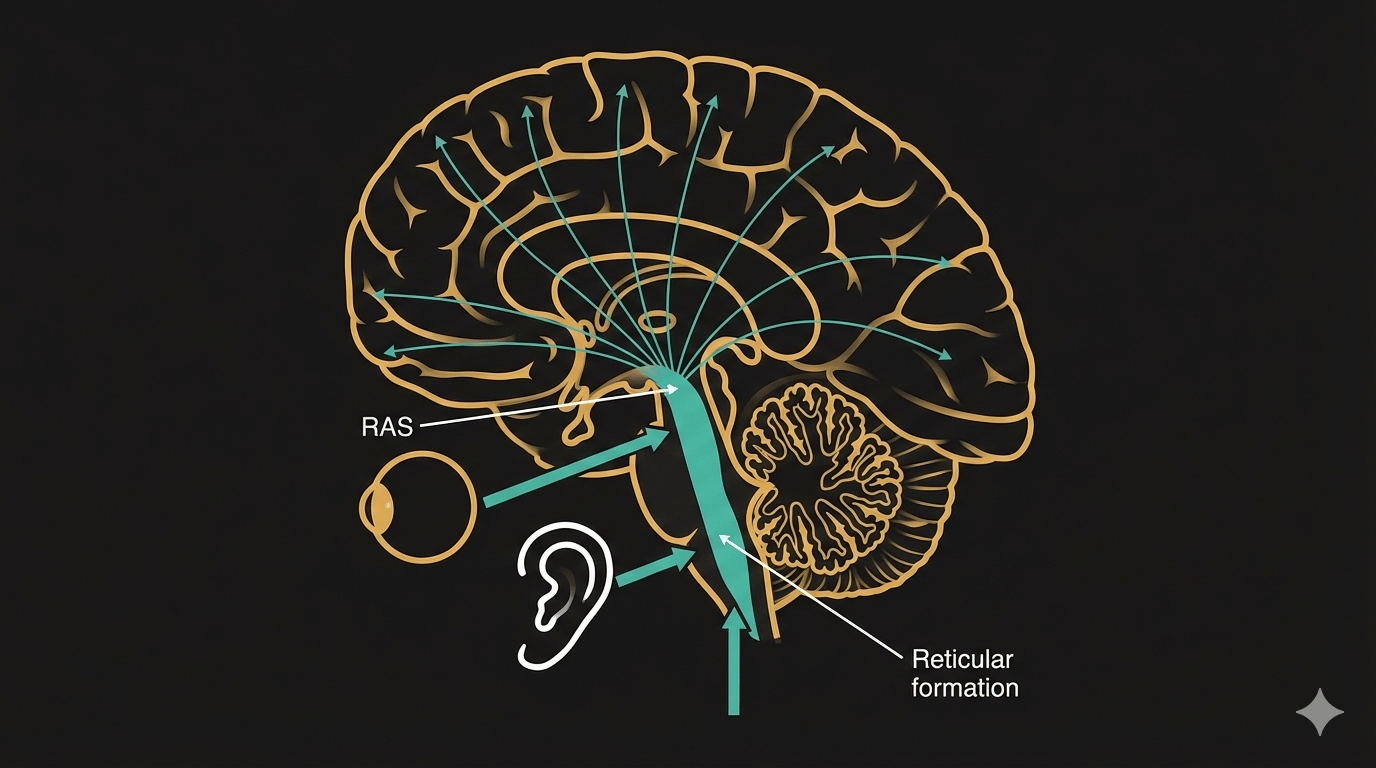

An infant's brain develops at an incredible pace, changing almost week by week during the first year of life. But it’s not just about getting bigger — the brain is also going through critical processes collectively known as cerebral development. One of the most important of these is myelination.

\

Myelination is the formation of a lipid-rich sheath around nerve fibers, which increases lipid content and reduces water. This process begins in the fifth month of fetal development and continues at full pace until about age two. In the central nervous system, myelin is found mainly in white matter, where it acts as an electrical insulator.

Healthy myelination allows for a rapid, reliable communication between neurons in the later years. If the brain develops more slowly than expected, it can lead to developmental delays. Тhe human brain is a complex system that requires careful attention from the very first days of life. Disorders can arise if brain growth is either too slow or too fast. \n \n Moreover, the complexity goes beyond growth rate. In some conditions, the brain's volume remains unchanged while its tissue density shifts. Whether myelination is abnormally slow or excessively fast (hypermyelination), it can create conditions that lead to neurological disorders.

\ Infants with abnormally slow myelination have a higher risk of developing cerebral palsy. Cerebral palsy is one of the leading causes of childhood disability that affects 2–3 out of every 1,000 newborns. Monitoring cerebral maturation in the first six months of life can be crucial for timely intervention. For patients at risk, acting quickly with the right therapies and rehabilitation can prevent damage and halt cell death.

\ On MRI scans, myelinated white matter stands out clearly from areas where myelination is incomplete. In patients under 12 months, however, distinguishing white matter from gray matter is often difficult. This is important because gray matter forms the cerebral cortex, the brain's hub for cognitive processes.

Through radiologists’ analysis, clinicians can study how nerve cells move through white matter toward the cortex, creating the brain's neural pathways. Observing these changes over time reveals whether the cortex is thinning or thickening and if the white matter is fully developed.